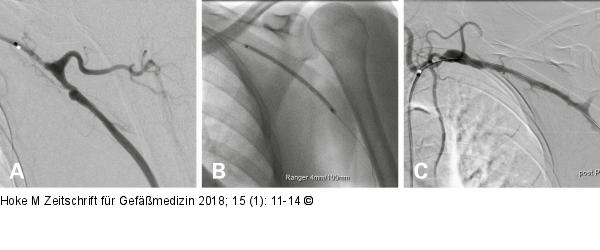

Abbildung 7A-C: Perkutane transluminale Angioplastie PTA einer linksseitigen A. subclavia/A. axillaris-Stenose (A) mittels DEB (B) bei einer 68-jährigen Patientin mit RZA mit gutem postinterventionellen Ergebnis (C). |

Abbildung 7A-C: Perkutane transluminale Angioplastie

PTA einer linksseitigen A. subclavia/A. axillaris-Stenose (A) mittels DEB (B) bei einer 68-jährigen Patientin mit RZA mit gutem postinterventionellen Ergebnis (C). |